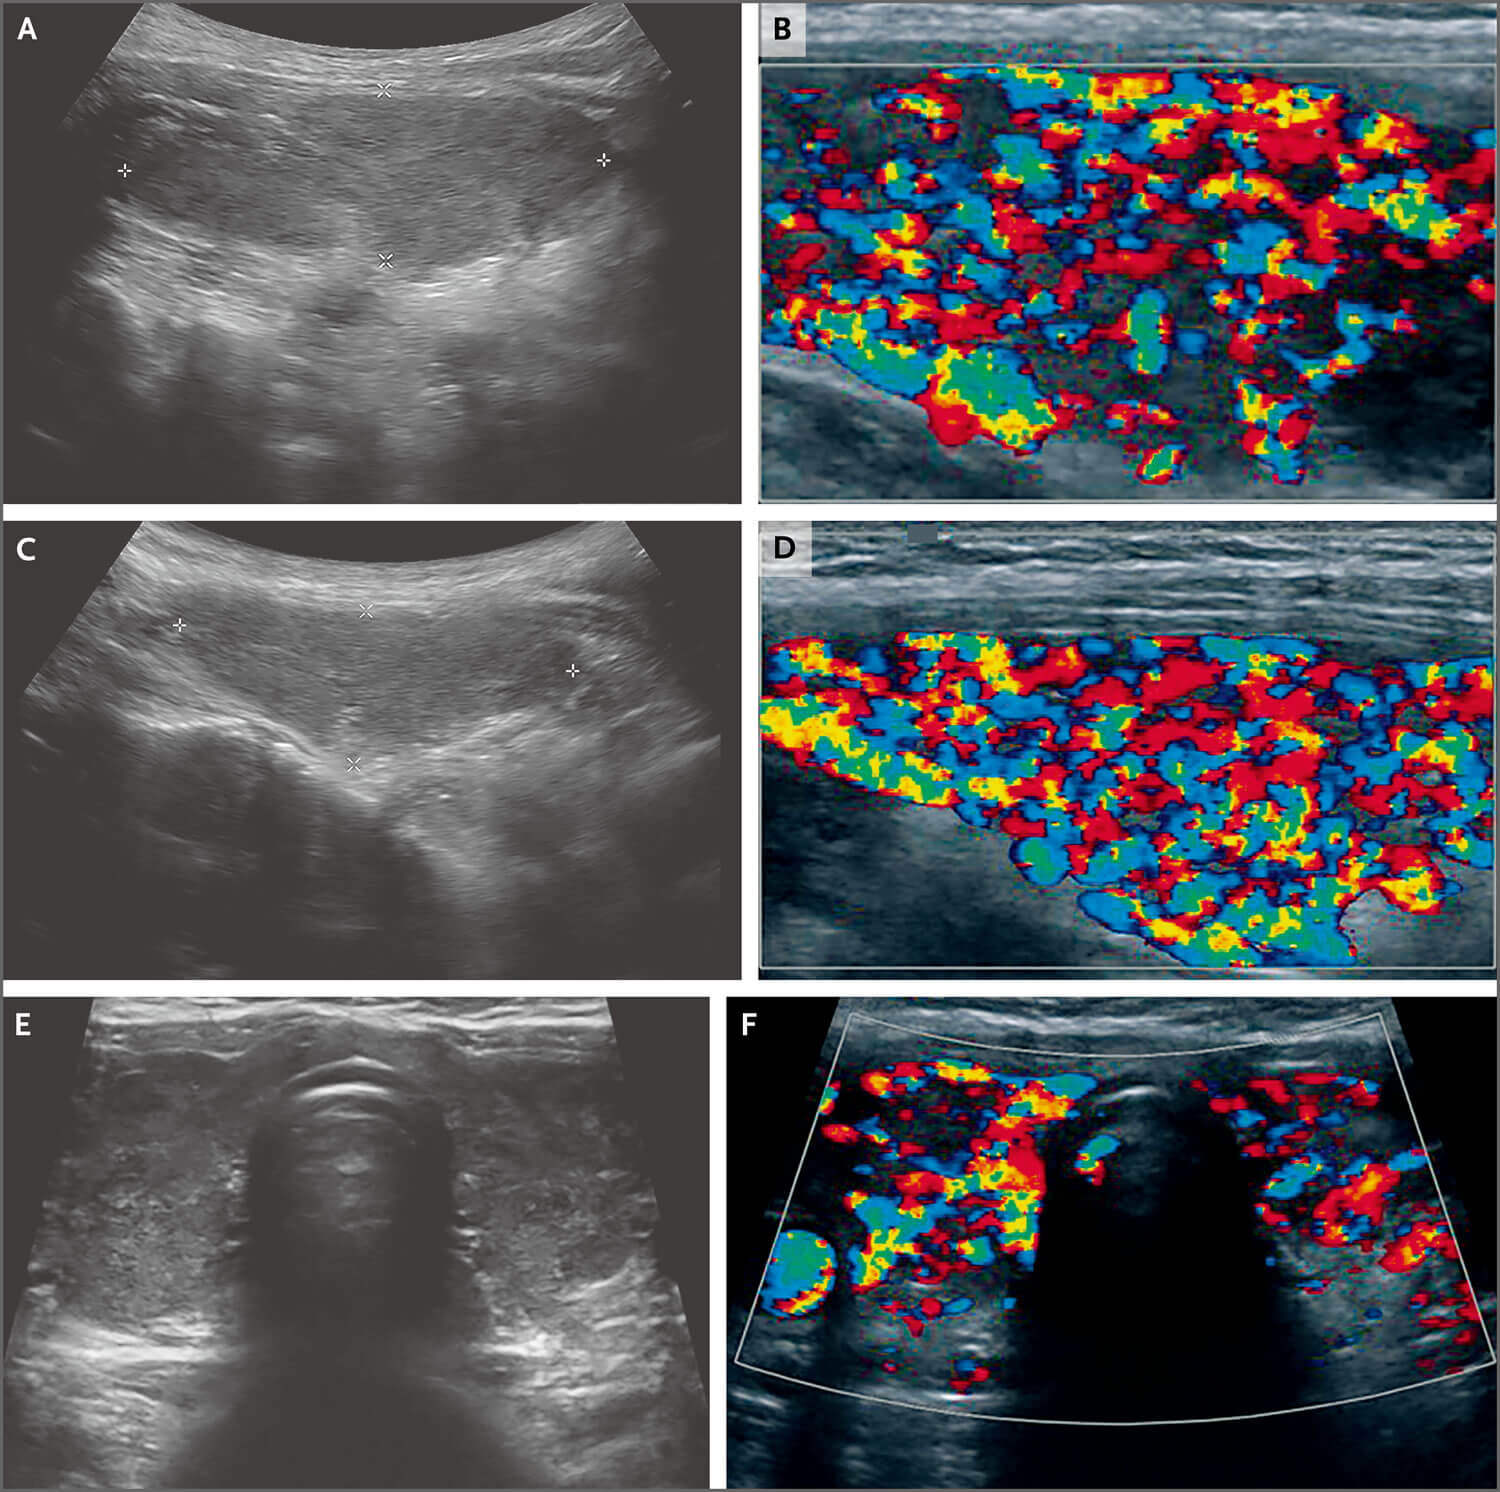

典型的火海征

典型"火海征"

超声:典型"火海征".

毒性弥漫性甲状腺肿内部血供丰富,呈"火海征",甲状腺上动脉流速>80cm